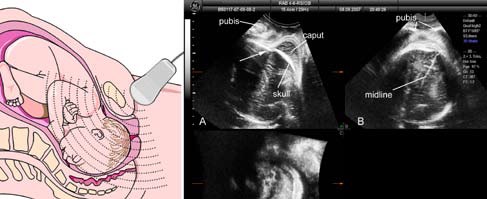

近年来,在第二产程中的经会阴超声已经应用于临床,被认为可以提高医生的能力,从而有效地评估胎头的位置及状态。

Dietz等最早开始通过会阴超声计算耻骨与胎头最低点之间的距离来评估产程进展。

Henrich等观察第二产程中产道内的胎儿下降情况,在矢状切面,胎头呈进行性的直接下降,在水平面和最终呈上仰。通过产妇骨盆的3D CT重建,可以观察到坐骨棘一般在耻骨下方3cm,这样就可以方便地对胎儿的状态进行预期的判断。最终的结果显示胎头上仰的方向可以较好地预测经阴道分娩的顺利程度,尤其是上仰的运动在生产过程中可以被影像学的方法实时评估并记录到。

Ghi及其团队对于第二产程中超声与指诊的相关性已经进行了评估,在矢状切面上,胎头方向与临床确认的状态有显著的相关性,而且,与骨盆轴有关的胎头中线旋转角度(被称为中线角)通过横切面的图像被评估到。尤其是在枕前位的病例中,中线角<45度与指诊+3cm之间有显著的相关性。

最近,连接胎头最低点与耻骨联合下缘之间获得的角度被认为是间接的、精确的,并且有很好重复性可以用来评估胎头下降的有效方法。Barbera等和Kalache等都证实当胎头进展角>120度或更多时,有非常高的概率可以顺利进行阴道分娩,或非常简单和方便地可以器械辅助娩出胎儿。

文献报道中更多的经验是通过标准的二维超声获得的,我们已经和GE医疗合作,来完成通过特定的三维超声软件(产程自动监测软件 SonoVCAD Labor)来评估第二产程中胎儿的位置及状态。评估的基础是通过超声容积图像的离线分析功能,获得更多的产妇与胎儿结构自动标记的精确校准,同时通过不同时刻容积图像的获取、对比与测量来更好地评估胎头进展的情况,以此获得第二产程中能否顺利进行自然分娩的有效信息。